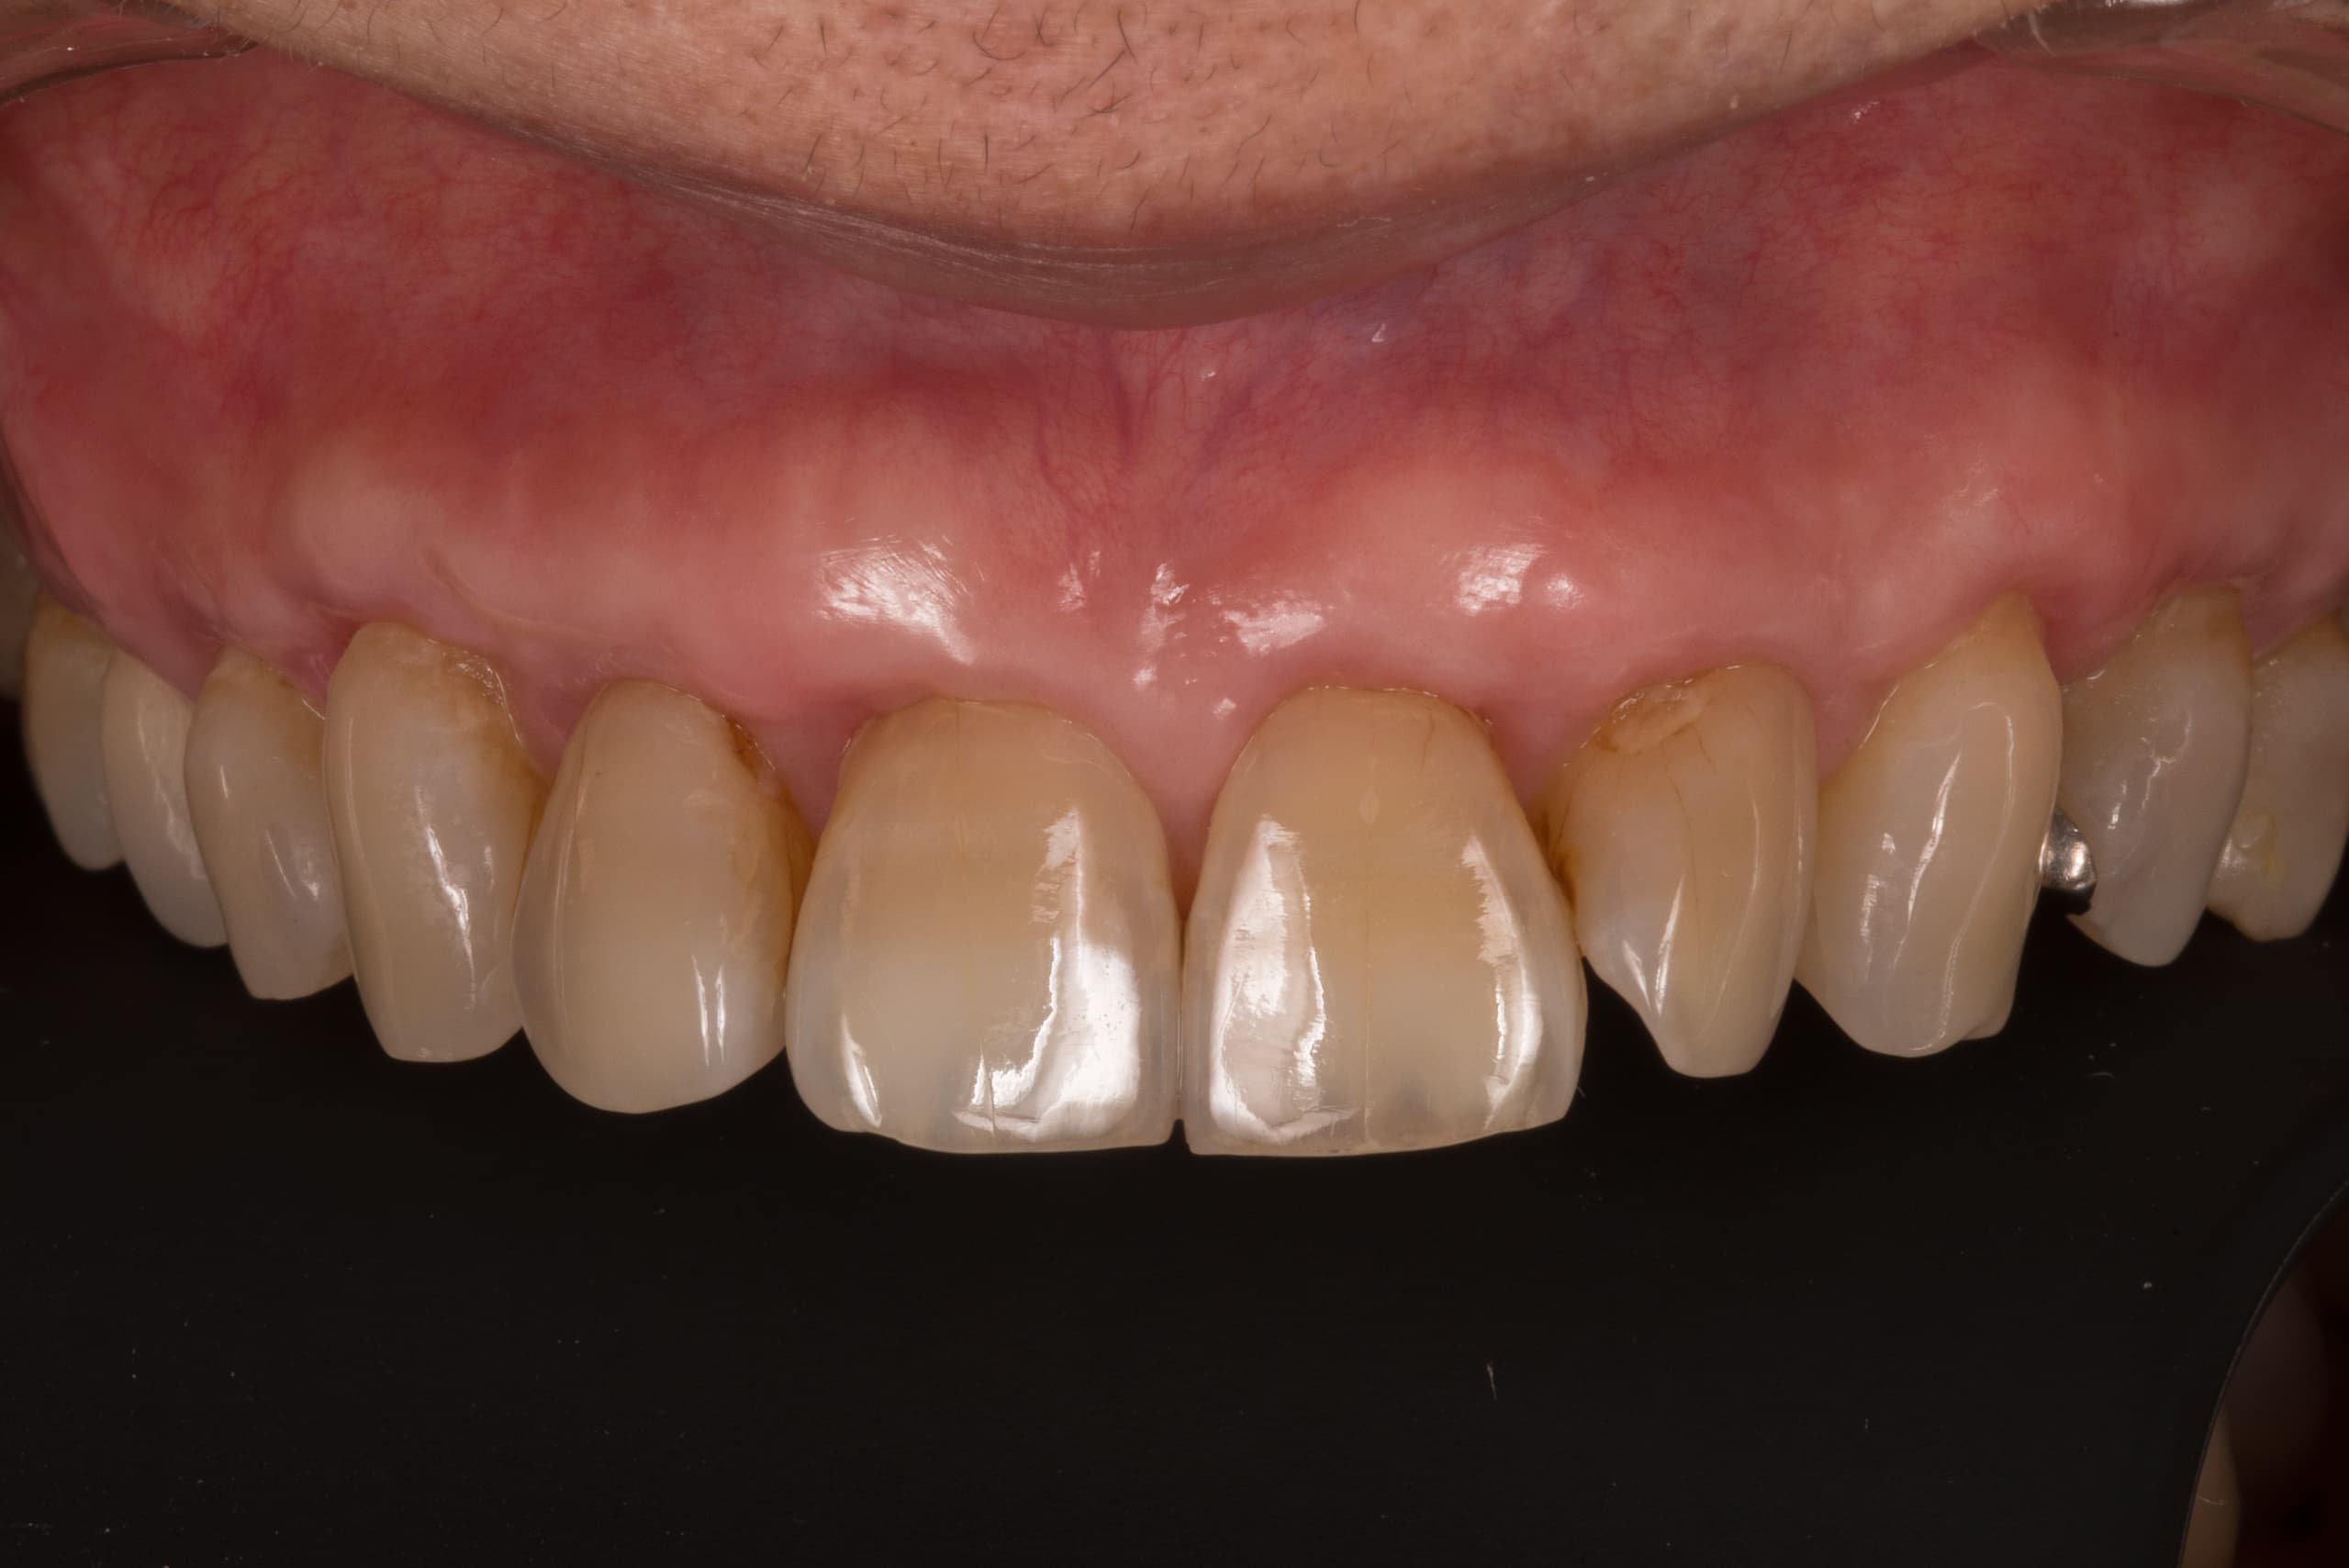

出来る限り歯を抜かない

一般的な歯周病(慢性歯周炎)に関する治療法は、ほぼ確立されています。私達は、出来る限り歯を抜かずに歯周病治療する事で歯を温存できるよう日々努力しています。

適切な治療を行えば、健康な口腔内を実現できます